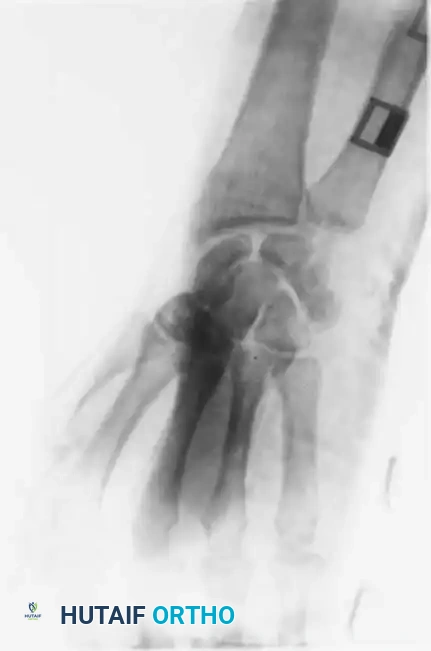

Fracture-dislocations of the proximal articular ends of the medial metacarpals are high-energy injuries that are notoriously underdiagnosed in the acute setting. Massive dorsal and ulnar soft-tissue swelling frequently obscures the gross clinical deformity. While all four medial metacarpals can dislocate either dorsally or volarly, the fourth and fifth metacarpals are the most frequently involved, with dorsal displacement being the predominant vector due to the pull of the extrinsic extensor tendons.

FOUR MEDIAL METACARPALS Surgical Diagram

The massive edema associated with CMC fracture-dislocations can mask the step-off deformity. A high index of suspicion must be maintained in any patient presenting with a crush injury or axial load to the clenched fist.

Radiographic Evaluation

Standard posteroanterior (PA) radiographs may appear deceptively benign. The hallmark of a CMC dislocation on a PA view is the loss of the parallel joint surfaces (the "M" line) at the carpometacarpal articulations.

A true lateral radiograph is an absolute necessity for accurate diagnosis, as it will clearly demonstrate the dorsal or volar displacement of the metacarpal bases relative to the carpal row.